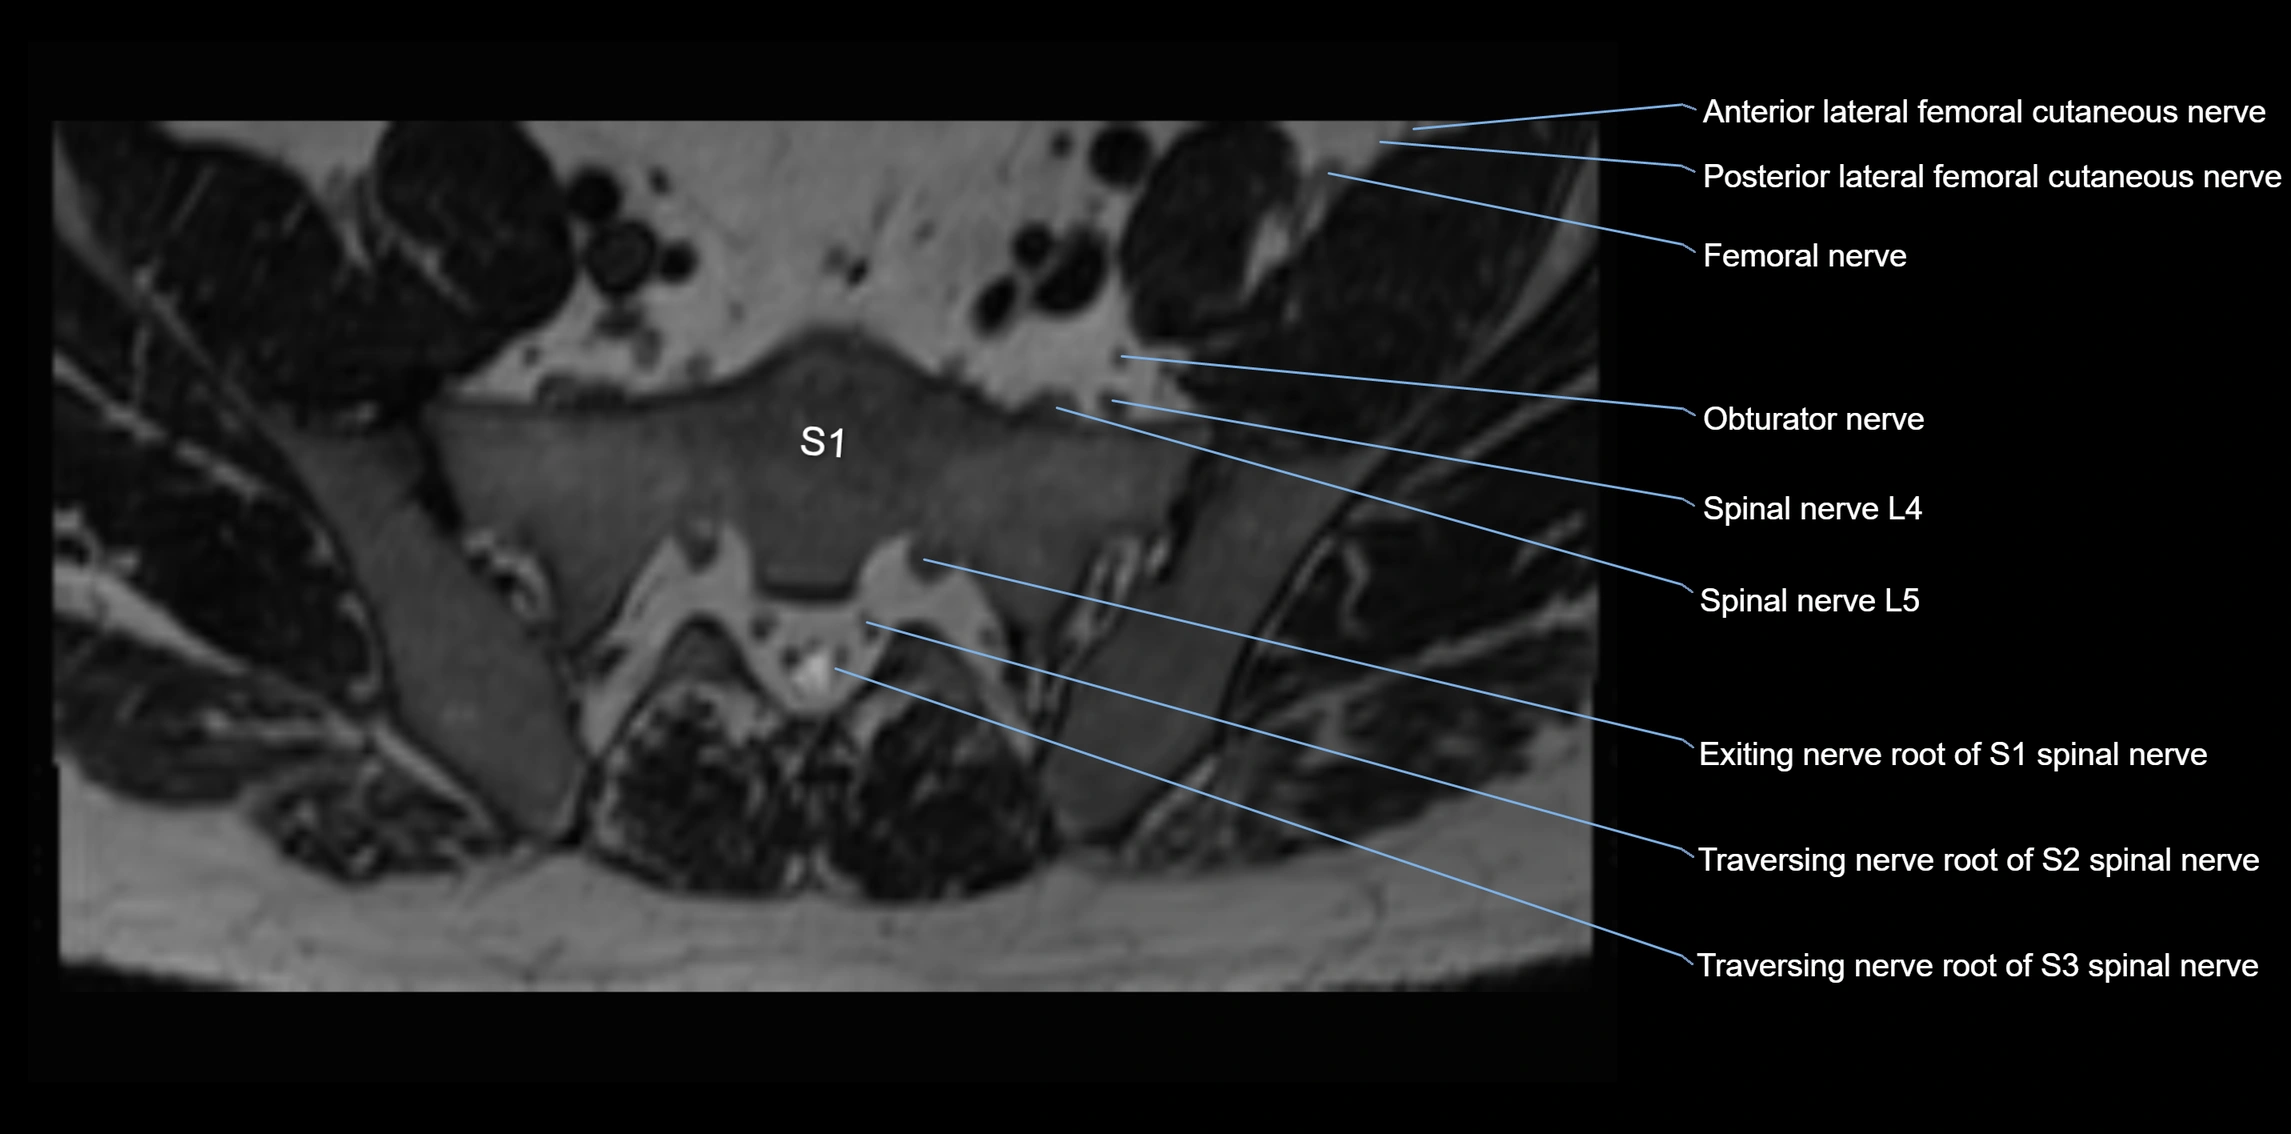

MRI image

image